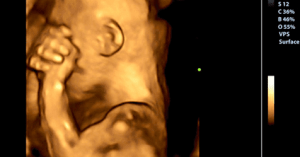

Essa pesquisa comprova que quando um bebê está dentro do útero materno, ele é um participante ativo do seu próprio desenvolvimento. Sobretudo porque durante essa fase ele está reunindo informações para a vida depois do nascimento.